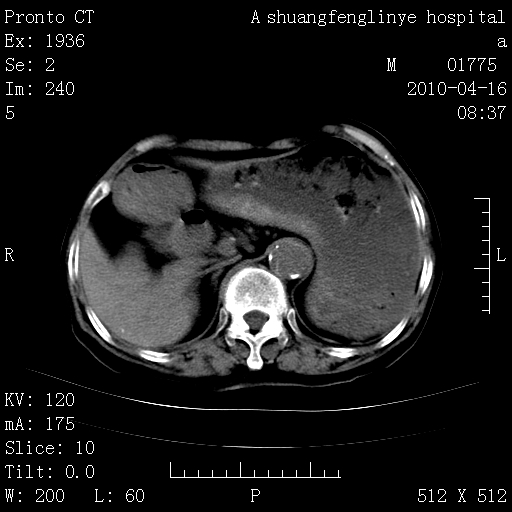

陈旧性结核,胃腔扩大,脾脏受压后移

慢支肺气肿,左上陈旧性结核,主动脉冠脉钙化

1)左肺上叶结核(纤维、增殖病灶)。2)冠状动脉及主动脉钙化。

1)左肺上叶结核(纤维、增殖病灶)。2)冠状动脉及主动脉钙化。肺动脉高压